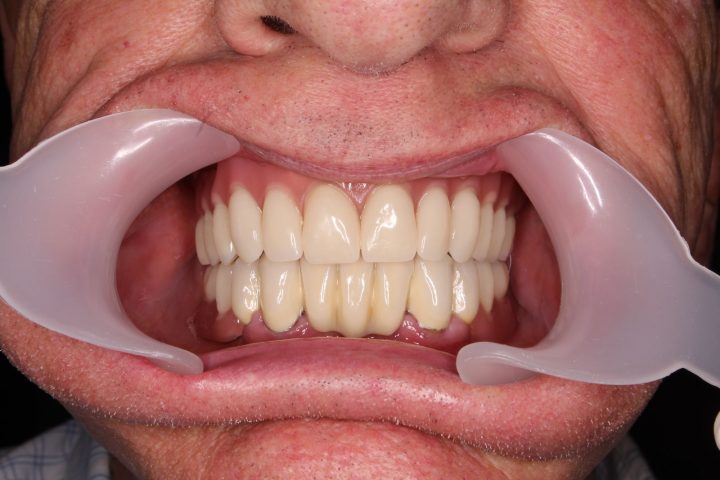

In der gleichen Behandlung hat er noch oben 4, und unten 6 Implantate bekommen, daneben hat er im Ablauf den 5 Tagen provisorischen Zahnersatz gekriegt.

Danach hatte er 4 Monate lange Heilungszeit, bald war den endgültigen Zahnersatz fertig: Oben wird eine Stegprothese auf 4 Implantate bearbeitet, unten wird eine Brücke auf 6 Implantate befestigt.